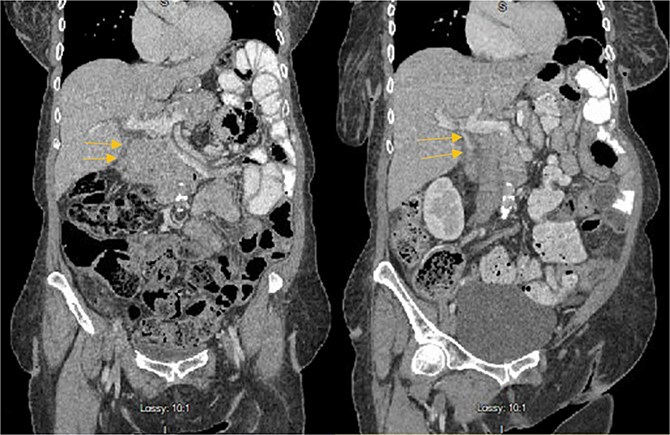

Stat CT scan showed new onset pericholecystic edema and hyperdense material within the common bile duct (CBD), not previously seen (Fig. 2). Stat Ultrasound confirmed findings of new onset acute cholecystitis (Fig. 3). Given the patient’s surgical history of gastric bypass, the decision was made to proceed with a robotic cholecystectomy with transcystic common bile duct exploration.